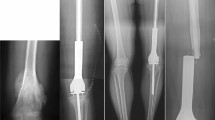

The following data were obtained: age at surgery, sex, BMI, symptom duration, stability and severity of the slip, and duration of follow-up. Patients were divided based on the symptom duration before diagnosis. Chronic slips are those causing symptoms for a period of at least 3 weeks, whereas acute slips are those that are symptomatic for < 3 weeks12. Patients were classified as either stable or unstable based on their ability to bear weight, even with crutches1. The severity of the slip was determined using the Southwick (SW) angle, measured as the angle between the proximal femoral physis and the femoral shaft on a frog-leg lateral radiograph (Fig. 3)31. The difference between these two angles obtained at the affected and unaffected sides is referred to as SW angles. A difference of < 30 degrees was graded as mild, a difference of 30 to 50 degrees moderate, and more than 50 degrees were graded as severe32.